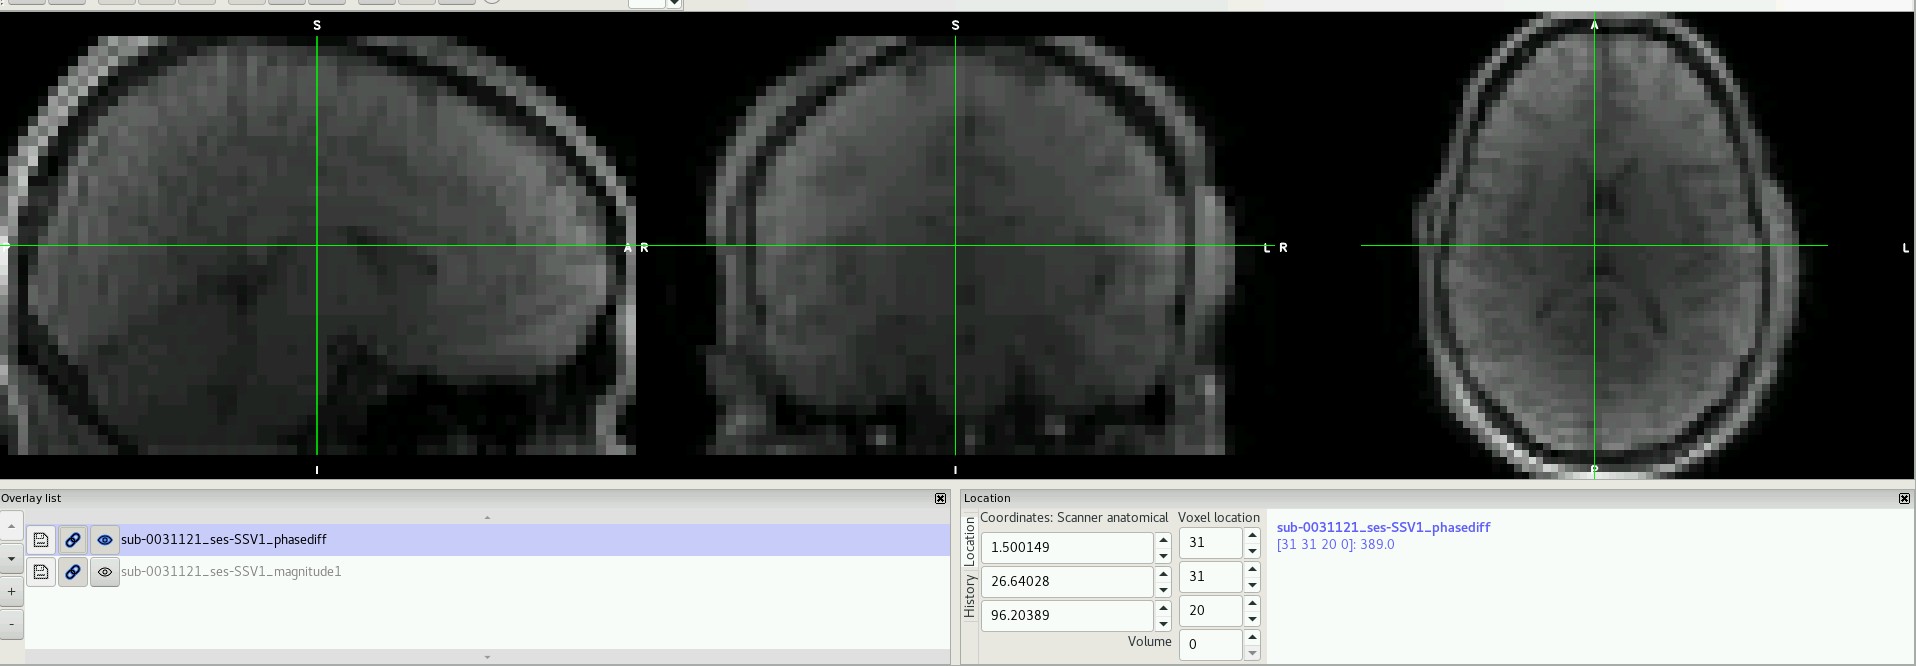

I have downloaded a set of publicly available data (Healthy Brain Network Serial Scanning Initiative) which contains a fieldmap folder for each subject. However, each of these folders contain a phase difference image with 2 volumes (not one) and a single magnitude image that does not resemble a "typical" magnitude image (see below).

I think you have this backwards. The first image is a phase difference, and the second contains the magnitude at each echo.